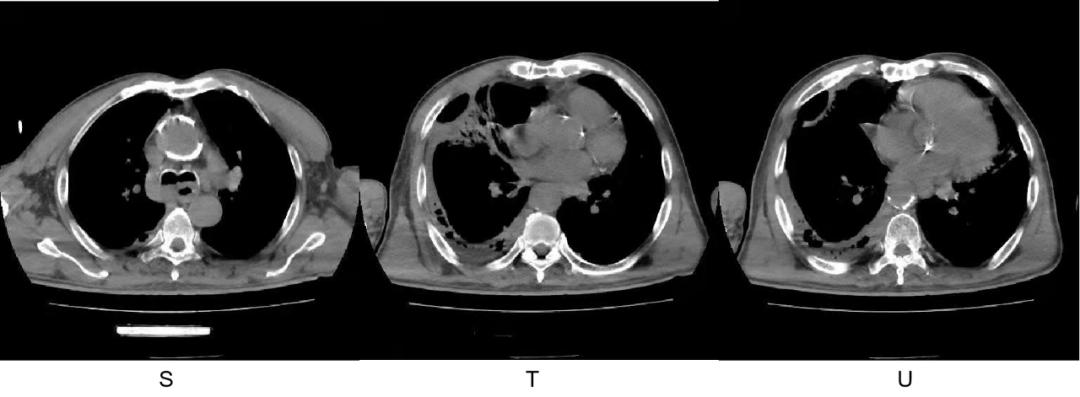

2022-1-2 入院时

2022-1-4 进展时复查 CT

2022-1-14 治疗后

原高张力肺脓肿及脓胸间隔 2 天病灶迅速进展,出现液气平面,大剂量青霉素+奥硝唑治疗 8 天明显好转。